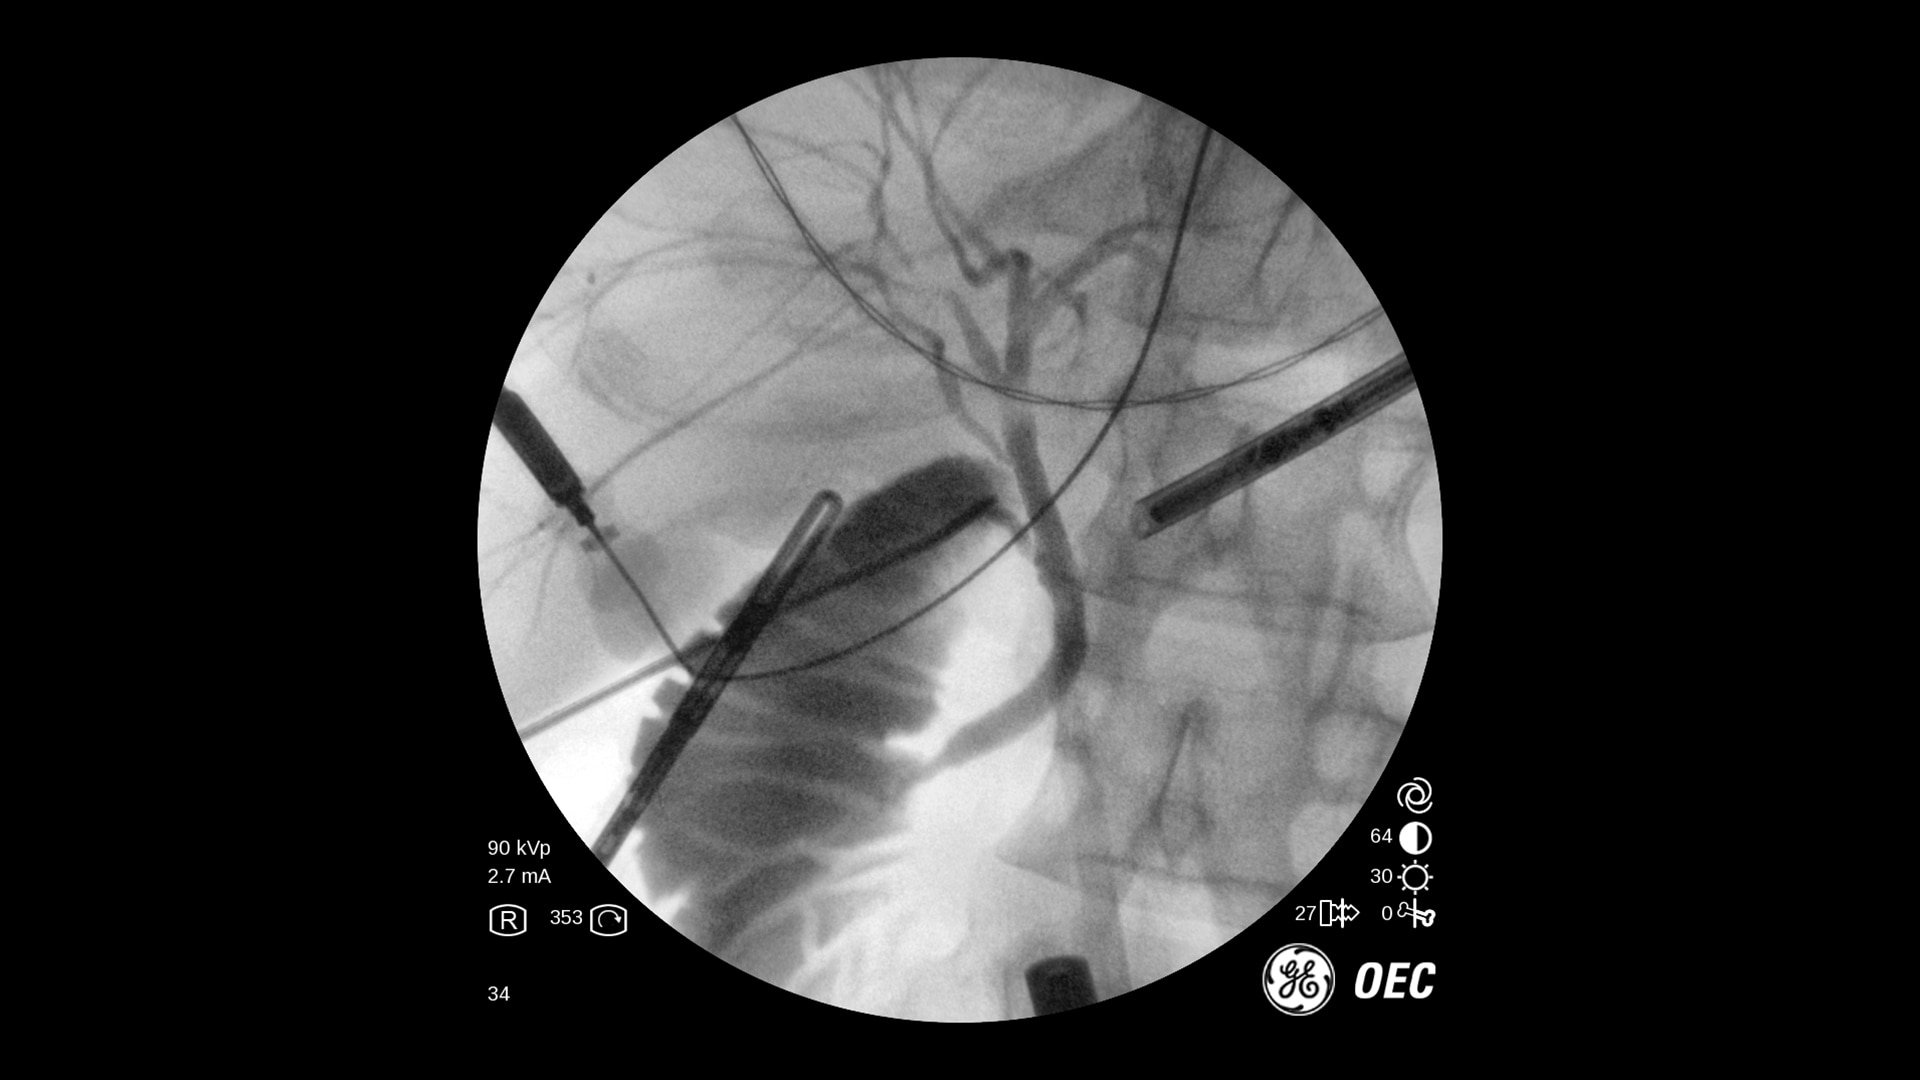

The OEC One all-in-one mobile C-arm offers superb imaging capabilities, made more accessible for a variety of procedures — from pain management to peripheral vascular. Enjoy image processing advancements in clear, detailed images.

Get the images you need without adjusting system settings from the first shot to the last shot with OEC image processing software.

OEC One utilizes automatic intelligence software to sense anatomy and provide high quality imaging at optimal mA and kV levels, even when anatomy is not properly centered in the field of view.